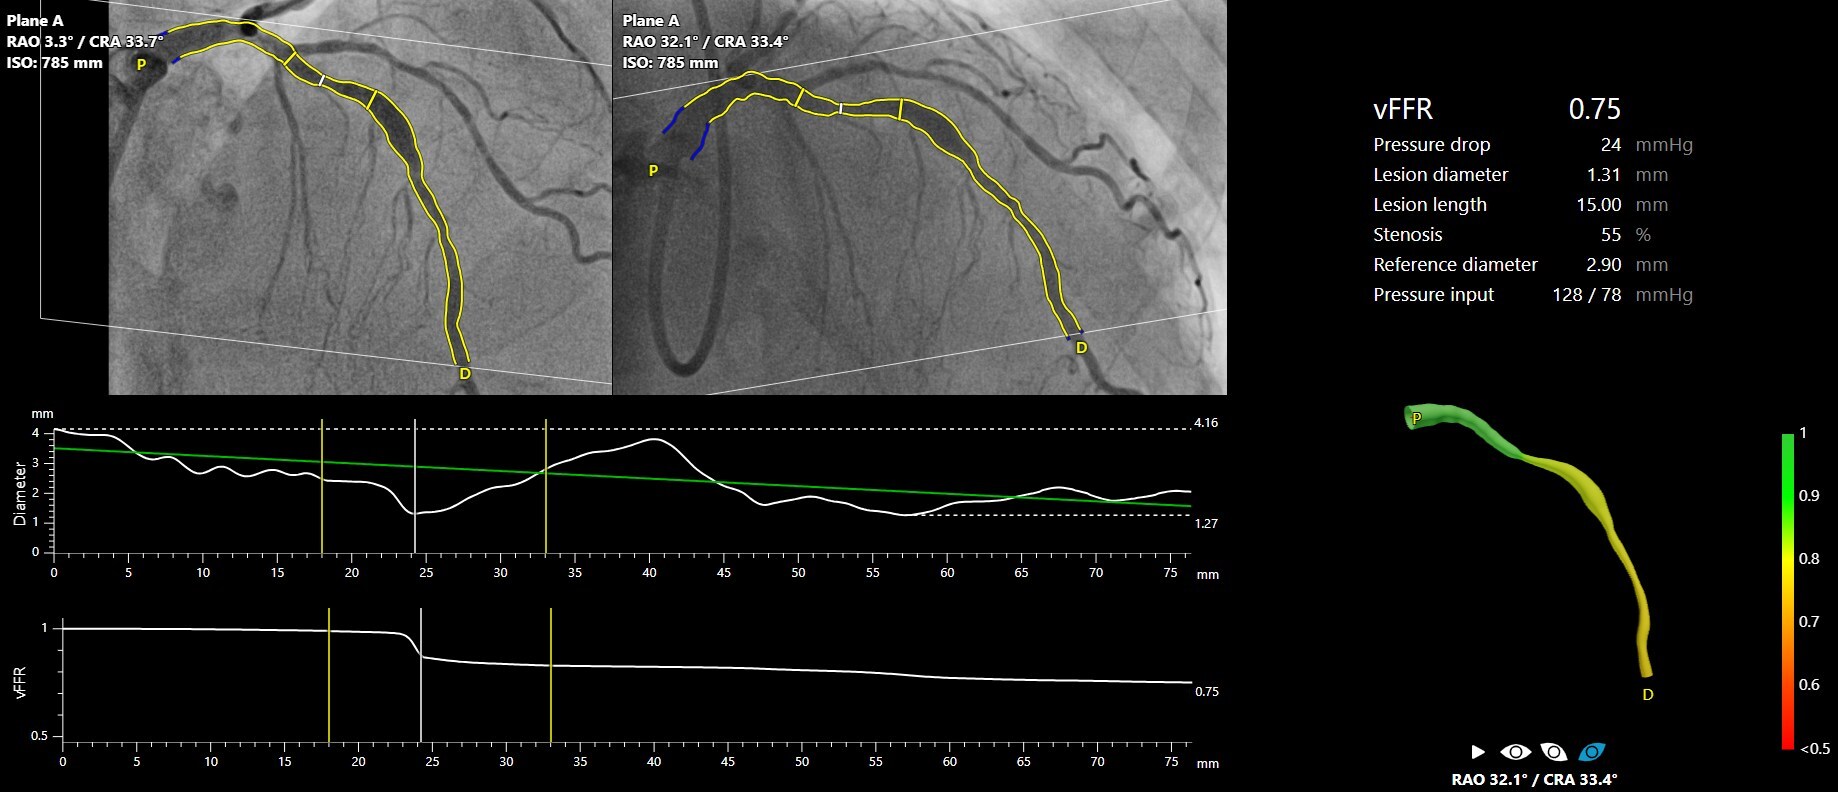

FAST III trial demonstrates non-inferiority of CAAS vFFR to invasive wire-based FFR